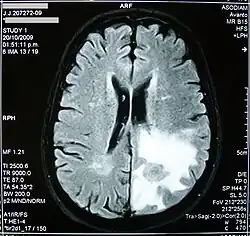

Edema cerebral

Edema cerebral é o acúmulo excessivo de líquido (edema) nos espaços intracelular e/ou extracelular do cérebro. Isso geralmente causa comprometimento da função nervosa, aumento da pressão dentro do crânio e pode levar à compressão direta do tecido cerebral e dos vasos sanguíneos. Os sintomas variam com base na localização e extensão do edema e geralmente incluem dores de cabeça, náuseas, vômitos, convulsões, sonolência, distúrbios visuais, tonturas e, em casos graves, coma e morte. Este incremento adiciona-se ao já provocado pela lesão primária, elevando a hipertensão intracraniana e propiciando as hérnias. O problema pode surgir tanto numa região delimitada como em todo cérebro. O diagnóstico e tratamento precoce são fundamentais para diminuir o risco de sequelas, melhorando o prognóstico. A abordagem de um edema cerebral quase sempre envolve a administração de diuréticos e corticosteroides.[1]